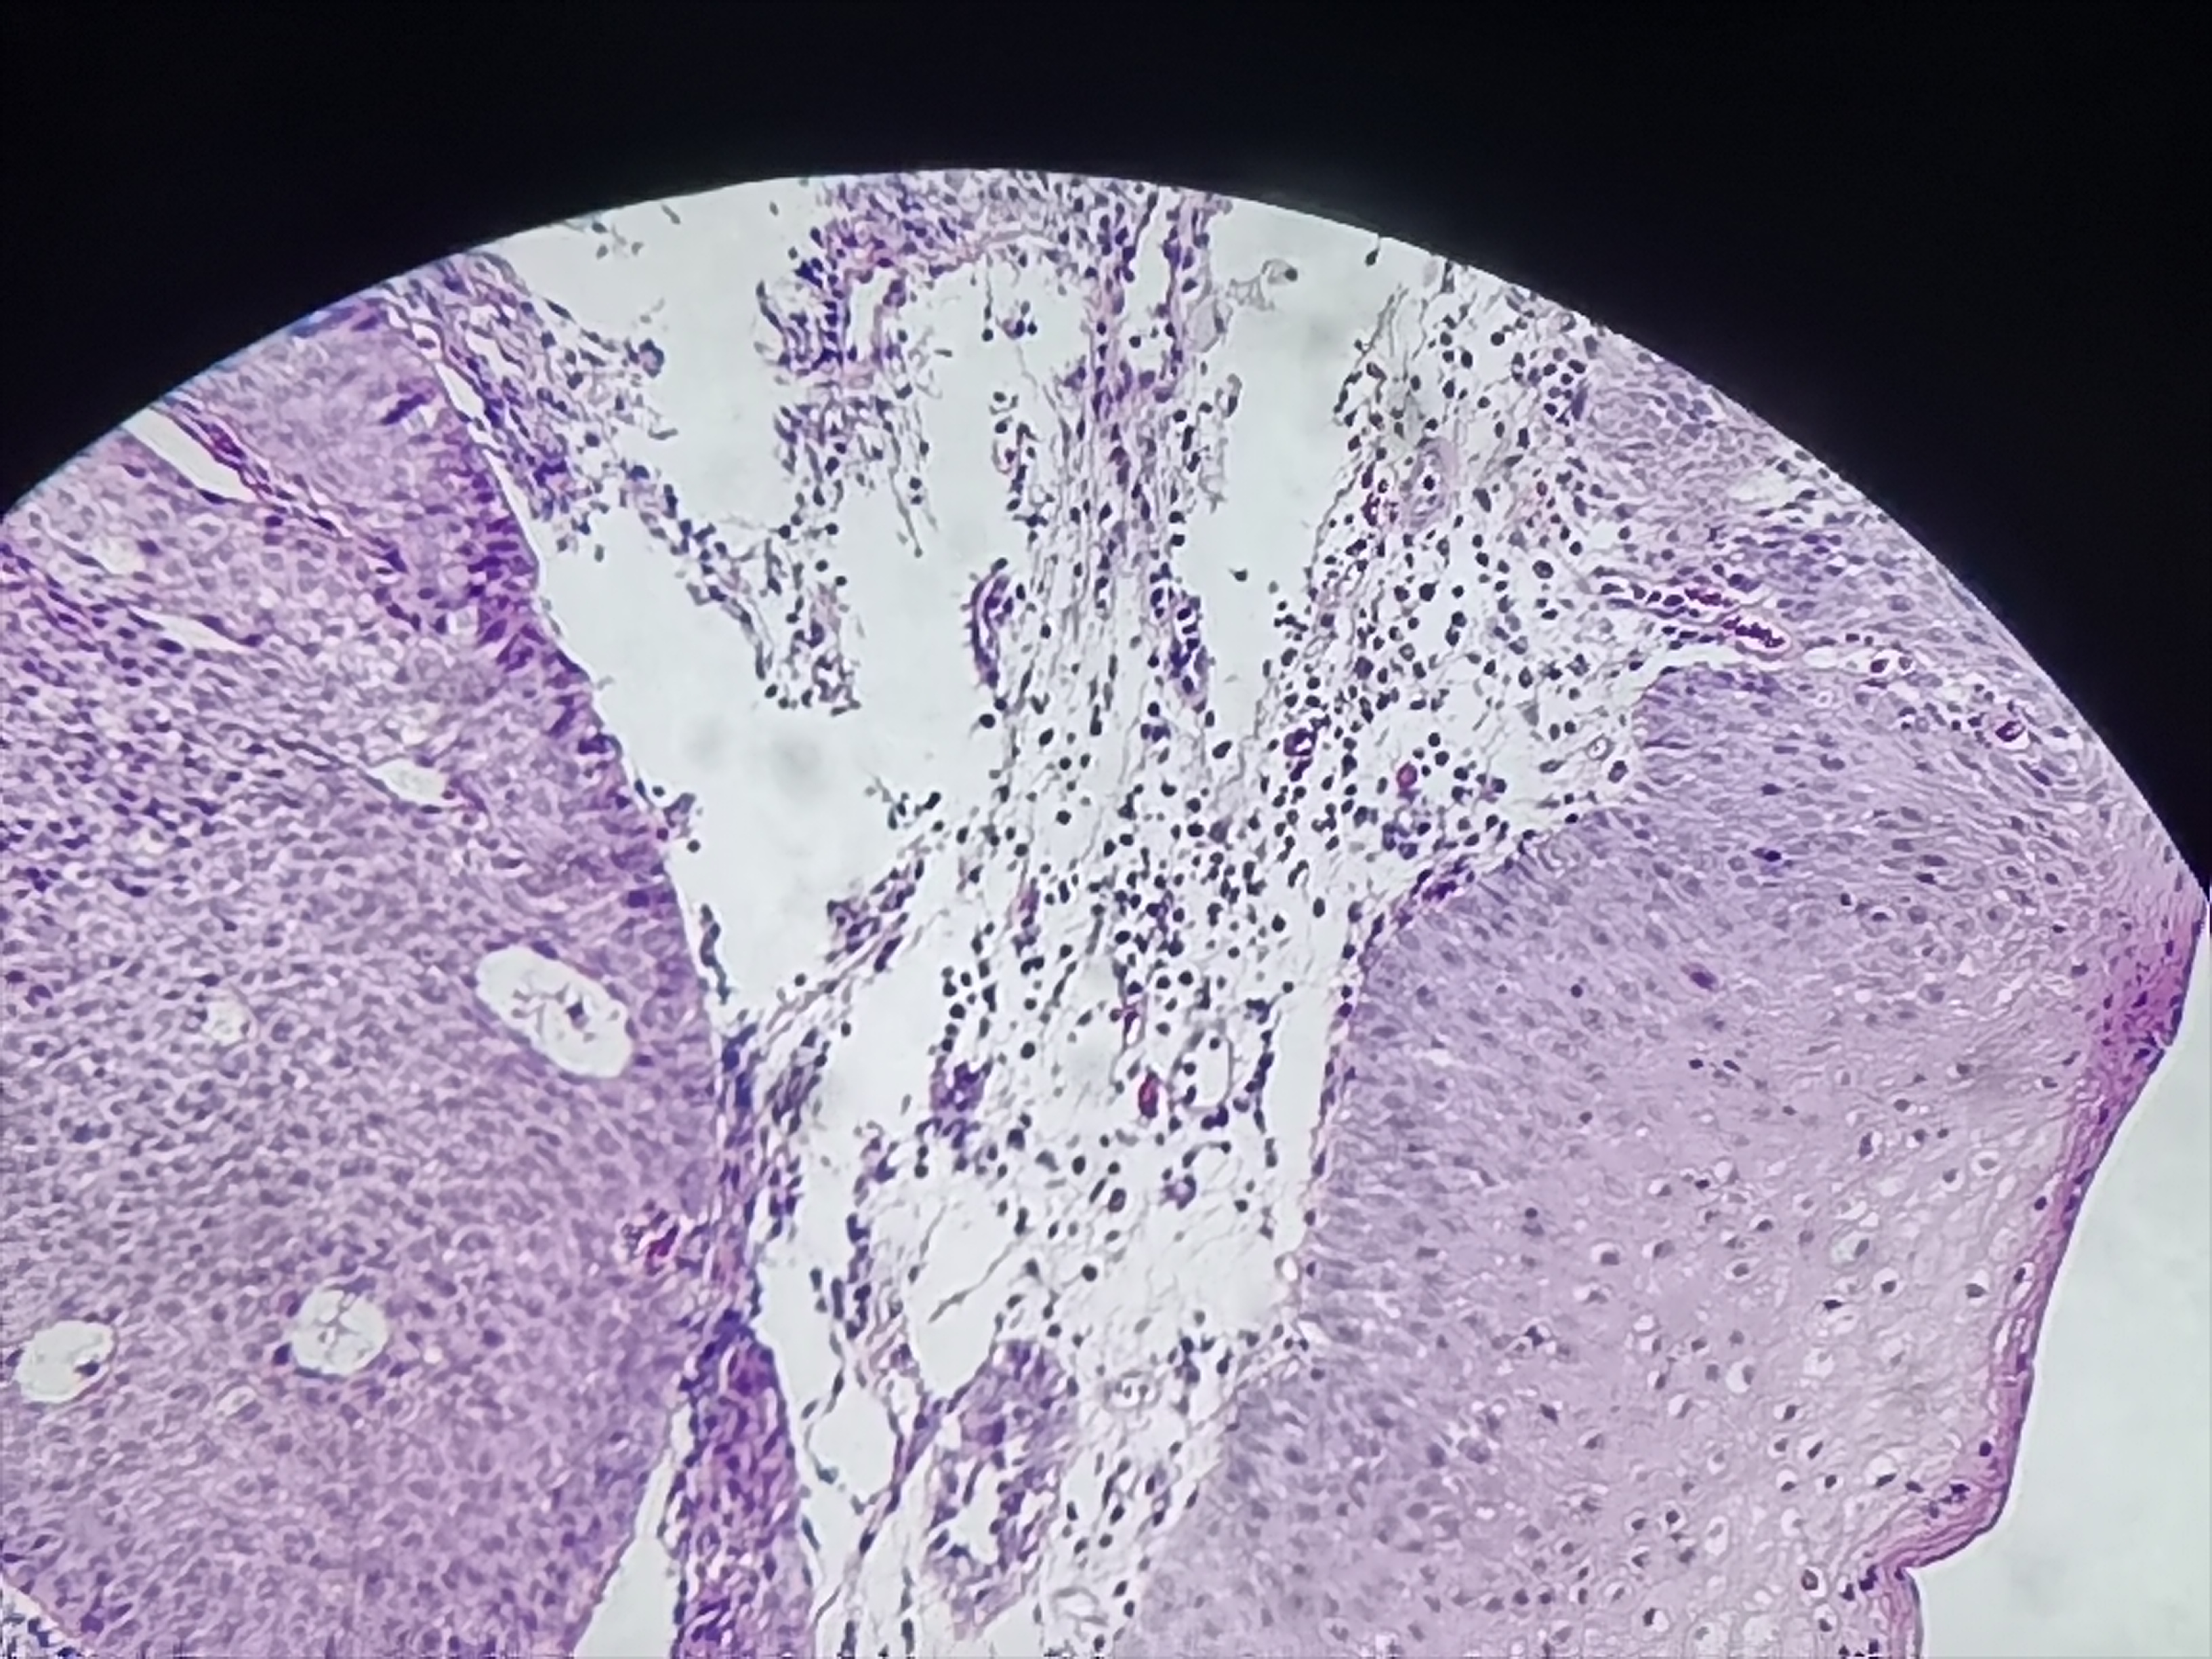

食管活检

性别

男

年龄

61岁

临床诊断

食管癌

一般病史

食管距门齿20cm处可见不规则病灶,质脆,易出血,管腔狭窄,镜子不能通过

标本名称

食管粘膜活检

大体所见

灰白色组织3块

考虑符合:鳞癌